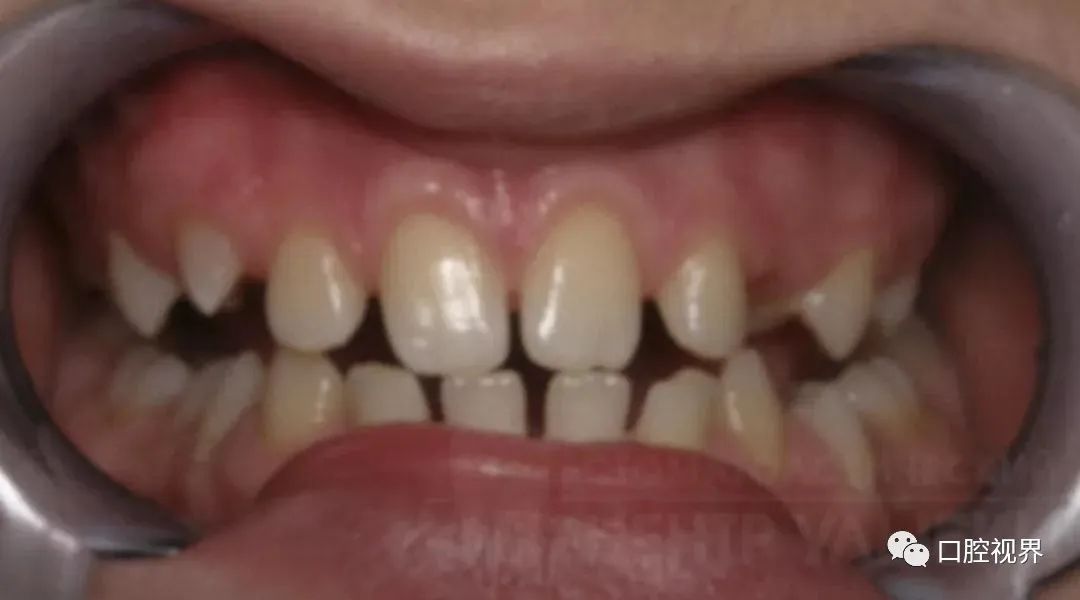

牙列畸形

牙列畸形会随着时间变得愈发严重。

譬如,牙齿原本就存在倾斜的状态,后期因为无数次的咬合使得牙齿倾斜程度越发严重,从而导致牙齿的缝隙也越来越大。